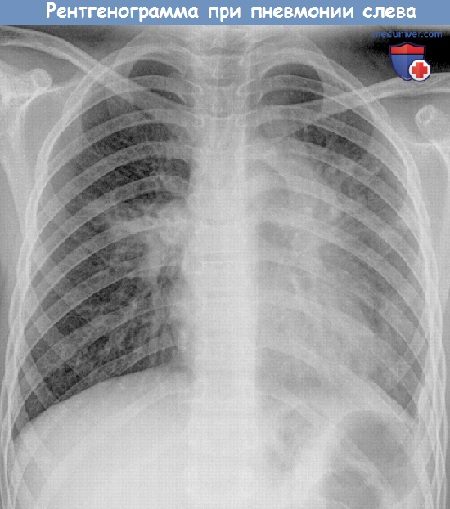

Как определить, что у ребенка воспаление легких? Как правильно лечить пневмонию у детей?Воспаление лёгких — опасная болезнь, поэтому ее нужно уметь правильно лечить. Особенно это актуально по отношению к малышам, так как согласно статистике, каждый год во всем мире от пневмонии умирают 1,4 миллиона детей в возрасте до 5 лет. Несмотря на достижения современной медицины, воспаление легких по частоте смертельных исходов занимает первое место среди всех инфекционных заболеваний. Пневмония или воспаление легких — это инфекционное заболевание, при котором поражаются самые нижние отделы дыхательной системы и нарушается функция легкого. Именно поэтому основным показателем пневмонии является не кашель и насморк, а одышка, потому что альвео-лярные мешочки при воспалении легких наполняются жидкостью или гноем, что затрудняет газообмен и вентиляцию в легких. Частое и кряхтящее дыхание ребенка — серьезный повод для обращения к врачу, даже если насморка и кашля при этом у него нет. В норме частота дыхания у детей в спокойном расслабленном состоянии должно быть следующим: — у новорожденных младше 2 месяцев — до 50 вдохов в минуту; — у малышей от 2 месяцев и до 1 года — до 40 вдохов в минуту; — у детей в возрасте 1-3 лет — до 30 вдохов в минуту; — у дошколят в возрасте 3 -7 лет — до 25 вдохов в минуту; — у школьников 7 -10 лет — до 20 вдохов в минуту. При воспалении легких эти показатели намного больше. Заболеть пневмонией ребенок может в любое время года, а не только зимой. Особенно опасна пневмония для малышей до 5 лет, иммунитет которых еще неокрепший, а организм их еще не умеет справляться с инфекцией. Пневмония редко бывает самостоятельной болезнью, чаще всего она развивается на фоне бронхита, сильной простуды и заболеваний горла из-за загустевания и плохого отхождения мокроты, препятствующей вентиляции легких. Причиной развития воспаления в легких могут быть вирусы, бактерии и грибки. Встречаются и смешанные воспаления, например, вирусно-бактериальные. По степени развития болезни пневмония может быть односторонней и двусторонней. Двусторонняя пневмония наиболее опасная, именно она является основной причиной детской смертности. К сожалению, многие родители ошибочно принимают пневмонию ребенка за обычную простуду и ждут, когда вот-вот ему станет лучше. И только тогда, когда ребенок уже становится сосвсем слабым, а его температура не падает даже после приема жаропонижающих средств, вызывают скорую помощь. Важно: если у ребенка высокая температура, он жалуется на боль в груди при кашле и дыхании, у него одышка, то обязательно надо вызвать врача, чтобы исключить воспаление лёгких. Специфические симптомы, по которым можно заподозрить пневмонию у ребенка, следующие: — он болеет гриппом или другой вирусной инфекцией уже 3-5 дней, а состояние его не улучшается или после незначительного улучшения температура поднялась снова; — жаропонижающие средства малоэффективны, они сбивают температура лишь на 30-40 минут ; — у него частое и шумное дыхание, одышка; — он часто кашляет, попытки сделать глубокий вдох каждый раз заканчиваются кашлем; — он слабый, постоянно спит и ничего не хочет кушать; — кожа у него стала бледной, а губы приобрели синюшный оттенок; — он жалуется на боль в животе и тошноту. Для диагностики пневмонии врач прослушивает дыхание ребенка стетоскопом, дает направление на сдачу анализа крови и прохождение рентгента грудной клетки. При пневмонии прослушиваются хрипы влажные и мелкопузырчатые, а при бронхите они сухие и свистящие. В последнее время для точной постановки диагноза «пневмония» терапевты используют результаты анализа крови на С реактивный белок. По результатам такого исследования можно определить, насколько сильно воспаление в легких. Если уровень С реактивного белка меньше 20 мг/л, то, скорее всего, у ребенка — бронхит, а воспаления в легких нет. Если же этот показатель приближается к 100 мг/л, то надо срочно сделать рентгеновский снимок, чтобы окончательно подтвердить диагноз «пневмония». Рентгенограмма при пневмонии у ребенка. Рентгеновский снимок — обязательный метод исследования при подозрении пневмонии (воспаления легкого). Лечение пневмонии зависит от типа микроорганизма, который способствовал ее развитию. Вирусная пневмония, которая развивается на фоне ОРВИ, считается более легкой формы. Она не требует длительного лечения и обычно проходит вместе с вирусной инфекцией. Чего нельзя сказать о бактериальной пневмонии. Ее обязательно следует лечить антибиотиками. Они помогают не только бороться с инфекцией, но и снижают температуру. Поэтому в данном случае жаропонижающие средства врач может и не назначить. Многие родители спрашивают врачей: «А можно ли лечить пневмонию ребенка дома?», так как не желают оставлять его одного в больнице. Биодоступность современных антибиотиков высокая, поэтому при легких формах пневмонии врач может разрешить лечить ребенка и дома, но отказываться от госпитализации, пренебрегая врачебных рекомендаций, при воспалении легких нельзя. Особенно если родители несвоевременно вызвали терапевта и пытались лечить ребенка сами, успев дать ему попробовать 2-3 вида антибиотика. В этом случае понятно, что таблетки ребенку уже не помогут, надо делать инъекции. Начатое на ранней стадии лечение воспаления легких помогает избежать тяжелых осложнений. Очень распространённая ошибка многих родителей — самостоятельно прекращать давать ребенку антибиотики. Полечились 3- 5 дней, температуры больше нет, и перестают давать лекарства, назначенные врачом. Этого делать ни в коем случае нельзя. Если врач назначил курс антибиотиков на 10 дней, значит, принимать их нужно именно столько времени, и ни днём меньше, даже если ребенок чувствует себя уже здоровым. Во время болезни ребенок отказывается от еды и не хочет пить. Это нормальное явление, указывающее на то, что организм «экономит» силы, чтобы бороться с недугом. Заставлять ребенка насильно кушать не нужно, а вот поить его водой надо часто и небольшими порциями. Она разжижает слизь в легких и выводит токсины из организма. Вместо воды можно ребенку дать настой шиповника, компот из сухофруктов и ягод, а также свежевыжатые соки, разбавленные водой 1:1. В период лечения пневмонии не нужно давать ребенку аптечные общеукрепляющие витаминные или иммуномодулирующие препараты. Они только увеличивают нагрузку на печень, которая во время болезни и так страдает. После окончания приема антибиотиков врач может назначить пробиотики, восстанавливающие микрофлору кишечника, сорбенты, чтобы ускорить очищение организма от токсинов и витаминное питание. В комнате, где лежит больной ребенок, должно быть чисто и свежо. Полезно там поставить увлажнитель воздуха, чтобы мокроты не пересыхали и не застаивались в легких, а ребенку было легче дышать. При правильном лечении пневмонии ребенок быстро восстанавливается. К нему возвращаются прежний аппетит, отличное самочувствие и хорошее настроение. Видео уроки техники аускультации легкихРекомендуем посмотреть другие видео ролики по пропедевтике Предлагаем ознакомиться со звуками аускультации легких:1. Везикулярное дыхание: 2. Бронхиальное дыхание: 3. Влажные хрипы: 3. Сухие хрипы: 4. Шум трения плевры: 5. Крепитация: 6. Жесткое дыхание: 7. Амфорическое дыхание: 8. Побочные дыхательные шумы: 9. Аускультация легких: — Вернуться в оглавление раздела «Пульмонология» Автор: Искандер Милевски Рекомендуем ознакомиться с тематичными статьями на нашем сайте:

Над зоной поражения отмечается укорочение перкуторного звука, при аускультации — бронхофония, ослабленное дыхание, иногда крепитация. Рентгенологически определяется усиление легочного рисунка между очагами воспаления и корнями легкого. В анализе крови определяется нейтрофильный лейкоцитоз со сдвигом влево, повышение СОЭ.

В четвертой стадии — стадии разрешения, — снижается температура, появляется частый кашель, появляются обильные разнокалиберные хрипы. На рентгенограммах также определяется стадийность процесса: в первой стадии — усиление сосудистого рисунка, ограничение подвижности диафрагмы; во второй стадии появляются плотные тени, соответствующие долям с вовлечением корня и плевры; в третьей и четвертой стадиях инфильтрация исчезает постепенно.

Диагностика проводится на основании клинико-рентгенологических данных.

- рентгенологически — очаговые, сегментарные, лобарные инфильтративные тени;